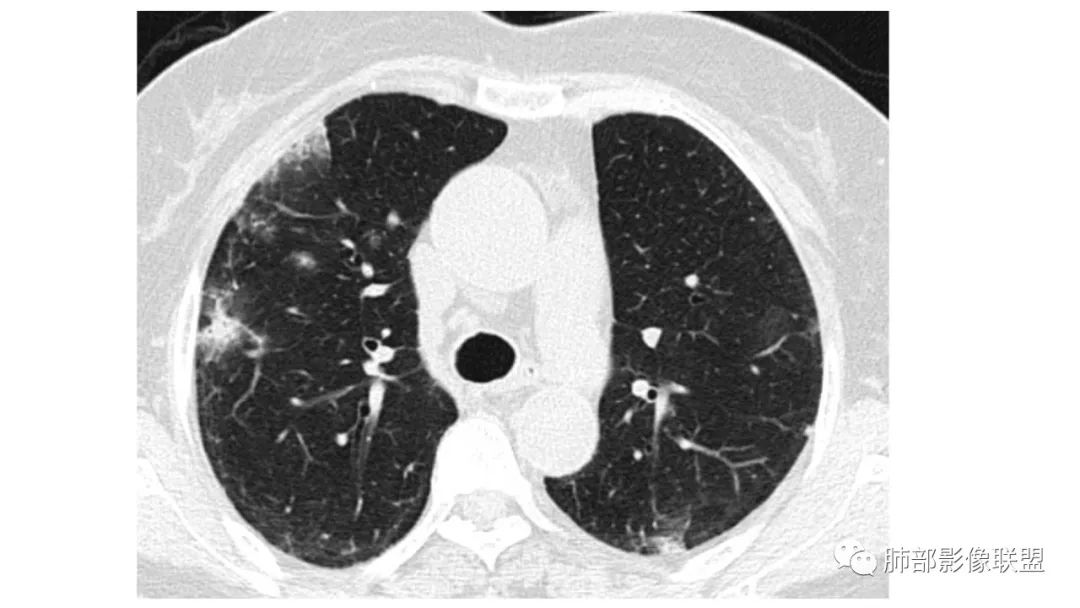

二、肺炎型

2、病灶常有一个主病灶,常位于下肺。后沿气道播散为多发病灶。

3、重力作用,叠瓦征。近叶间裂因重力效应,呈膨隆改变。

4、增强后不均匀强化,存在低强化区呈弱强化或无强化,因此可见“血管造影征。”血管毛糙与肺炎有统计学差异。

5、支气管粗细不均,呈“枯树枝征”,但与肺炎这一点鉴别不具有统计学差异。可发生支气管扩张

6、空腔形成,部分蜂窝状改变。

8、斑片常伴有结节,边缘清楚GGO或欠清楚。

9.粘液腺癌的变化规律:结节缓慢发展而来,向周围播散形成斑片后可快速进展,有时支气管镜后或粘液排出后局部可形成好转的假象。病灶可沿肺泡和支气管播散。

三、本例是一个误诊多年的病例,给我们很多启示:

2.粘液腺癌易伪装成肺炎的形态,尤其是当患者本身具有免疫色彩的时候,易误诊为间质性肺炎,或肺部感染。若治疗无效,取得病理很重要。

4.回到本例,左下肺病变两次好转,均未经过肿瘤治疗,第一次是支气管镜后,第二次是当其他病变都在进展的情况下,左下肺病变范围反而缩小趋于浅淡。